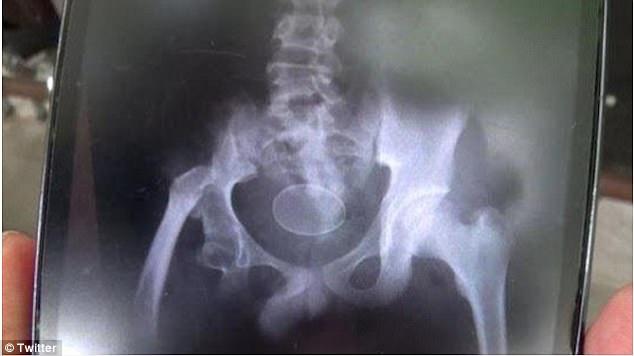

Ο 14χρονος πρωταγωνιστής της ιστορίας είναι ο Ακμάλ Ρουσλί, ο οποίος μεταφέρθηκε την Τρίτη στο νοσοκομείο με έντονους πόνους στην κοιλιά. Όταν οι γιατροί του έκαναν τον απαραίτητο υπέρηχο, διαπίστωσαν πως μέσα στην κοιλιά του 14χρονου αγοριού, υπήρχαν δύο… αυγά κότας.

Τον ρώτησαν αν τα κατάπιε και το αρνήθηκε. Οι γιατροί τον πίστεψαν, καθώς τα αυγά ήταν ολόκληρα στην κοιλιά του. Τελικά, οι γιατροί αφαίρεσαν με επέμβαση τα δύο αυγά από την κοιλιά του 14χρονου, ωστόσο, ο πατέρας του τους ενημέρωσε πως όταν το παιδί ήταν 12 ετών είχε μεταφερθεί με έντονους πόνους και πρήξιμο στο νοσοκομείο και οι γιατροί διαπίστωσαν ότι υπήρχαν 18 αυγά μέσα στην κοιλιά του, αλλά και στο έντερο. Σε εκείνη την περίπτωση, τα αυγά αφαιρέθηκαν από το παιδί μέσω του πρωκτού και του χορηγήθηκε ειδική αγωγή.

«Η αρχική μας υποψία ήταν ότι τα αυγά σκοπίμως εισήχθησαν μέσω του πρωκτού στο εσωτερικό του σώματος του παιδιού. Στις εξετάσεις που κάναμε, ωστόσο, δεν διαπιστώσαμε κάτι τέτοιο.

Είναι παράδοξο. Τα αυγά κότας δεν είναι δυνατόν να σχηματιστούν μέσα στο ανθρώπινο σώμα και στο πεπτικό σύστημα», δήλωσε ένας από τους θεράποντες ιατρούς του παιδιού.